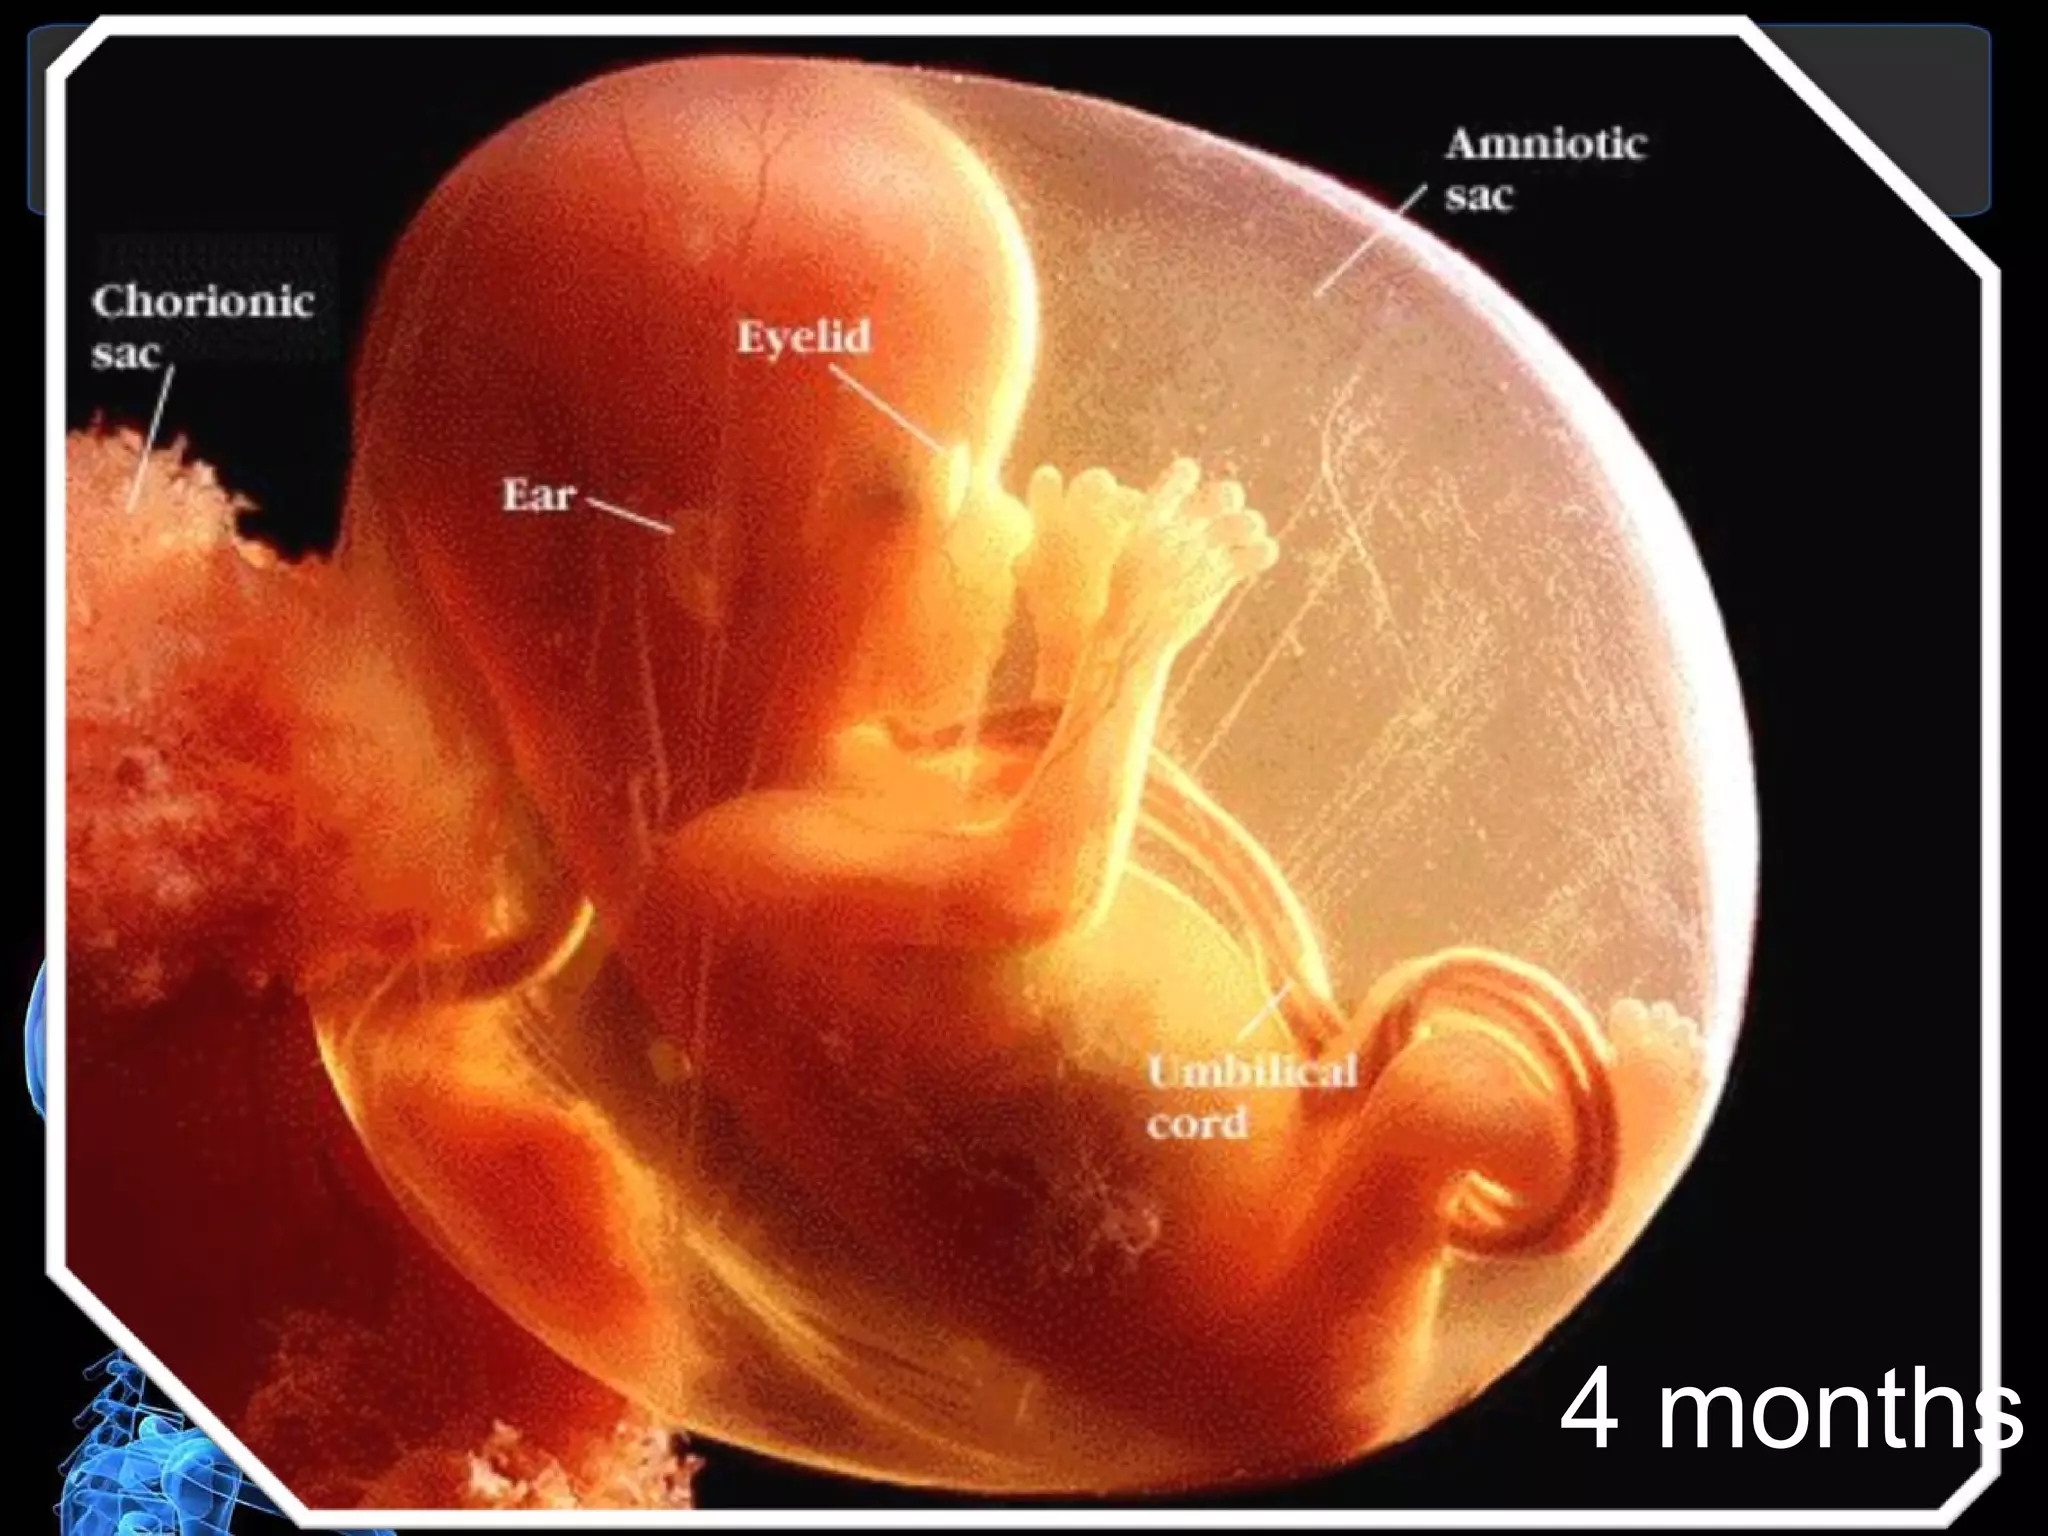

4 months

Month 4  Second Trimester At the end of 4 months:   Baby is 6 1/2 to 7 inches long  Weight is about 6 to 7 ounces  Baby is developing reflexes, such as sucking and swallowing and may begin sucking his/her thumb  Tooth buds are developing  Sweat glands are forming on palms and soles  Fingers and toes are well defined  Sex is identifiable  Skin is bright pink, transparent and covered with soft, downy hair  Although recognizably human in appearance, the baby would not be able to survive outside the mother's body